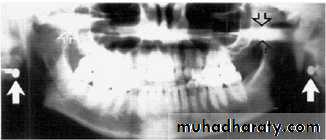

Stud earrings, real shadows (solid arrows)

with ghost shadows (open arrows).

Tongue bar projected over palate

Neck collar artifact

A necklace